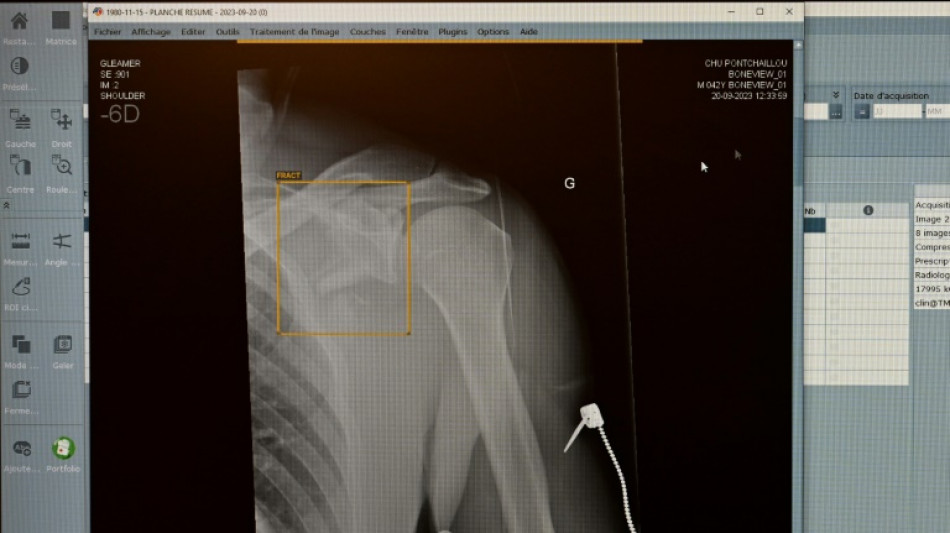

Jeder Zweite kann sich vorstellen, eine Anwendung mit Künstlicher Intelligenz (KI) bei Gesundheitsproblemen um eine Zweitmeinung zu ersuchen. Nach einer am Dienstag in Berlin veröffentlichten Umfrage des Digitalverbandes Bitkom ist das für 51 Prozent der Teilnehmenden eine Option.

Fast die Hälfte der Befragten (47 Prozent) traut einer KI laut Befragung in bestimmten Fällen sogar bessere Diagnosen zu als Menschen. Auf der Suche nach Informationen zu Diagnosen, Nebenwirkungen verordneter Arzneimittel oder zur Abklärung von Symptomen haben sich demnach sechs Prozent schon einmal bei einer KI bedient - etwa über Symptomchecker-Apps oder Chatbots wie ChatGPT.